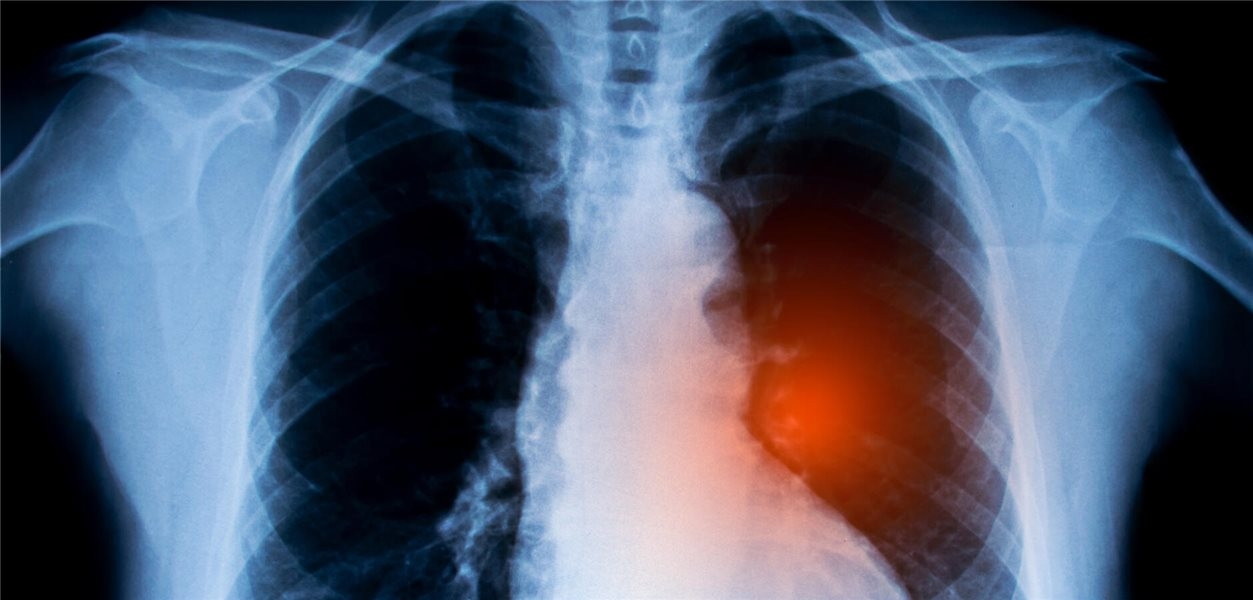

Nicht-kleinzelliges Lungenkarzinom: Krebsimpfstoffe könnten Überlebenschancen erhöhen

Für Menschen mit fortgeschrittenem nicht-kleinzelligem Lungenkarzinom kommen nach der Erstlinientherapie auch Krebsimpfstoffe in Frage. In einer Metaanalyse wurde deren klinische Wirksamkeit untersucht. Besonders eine Patientengruppe schien zu profitieren.